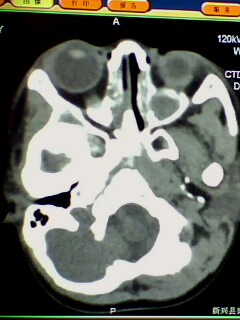

腺样体肥大,双侧上颌窦炎症,原因支持楼主。乳突体位不正,个人发育有差异,观察吧。

腺样体肥大,右侧扁桃体炎,双侧上颌窦炎症(鼻窦炎)

腺样体肥大,副鼻窦炎症。支持!乳突尚未发育完全,加上位置不标准不好说。

支持鼻咽增殖体肥大、双侧上颌窦炎。

1)鼻咽腺样体肥大。2)双侧上颌窦、双侧筛窦及双侧蝶窦炎症。